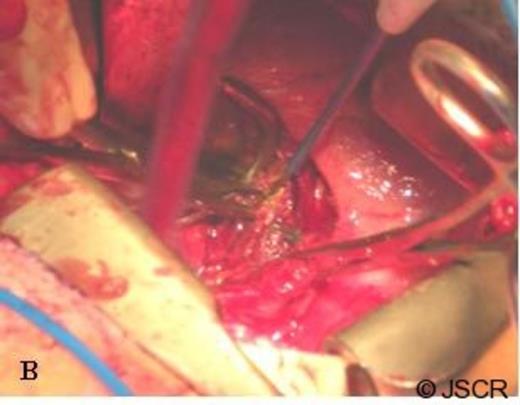

The second stage of the procedure was carried out through double thoracotomy incisions – a thoracotomy through the 5th intercostal space for resection of her pulmonary metastases and an additional thoracotomy through her 8th intercostal space to provide adequate exposure for retroperitoneal dissection of her right adrenal gland. Following the wedge resections of her right lung metastases, dissection was begun to resect the right adrenal gland. A firm mass was palpable prior to incising the diaphragm, and it appeared that the adrenal metastasis had invaded the diaphragm locally. A 3cm x 3cm portion of diaphragm was incised and dissection was carried down around the liver and the adrenal mass was excised from the caudate lobe. The cancer was noted to be invading the wall of the IVC, and therefore, a vascular surgeon was consulted to assist in completion of the resection. Proximal and distal control of the IVC was obtained (Figure 1).

Dissection of the caudate lobe of the liver to gain proximal and distal control of the IVC. The tumor is being retracted cephalad with a clamp.